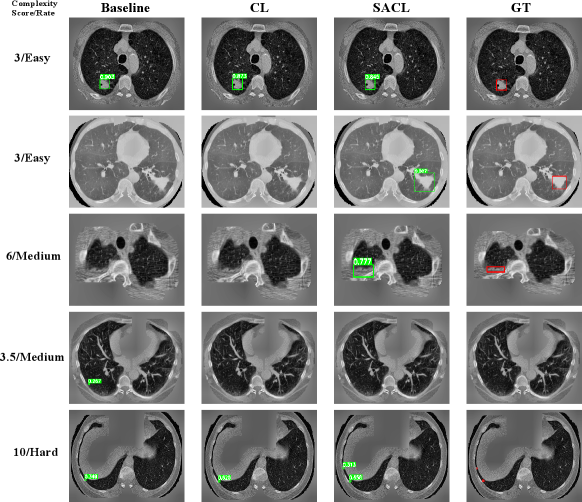

Refer to caption

Fig. 2: Detection results comparison using 10% of training data. The first column shows the complexity score/rate for each case. The subsequent columns show results from different models: baseline, CL, SACL, and ground truth. Each row represents the same case. Green boxes indicate model predictions with confidence scores, red boxes show ground truth annotations. Absence of red boxes indicates negative samples, while absence of green boxes indicates the model predicted negative.

As illustrated in Figure 2, the visualization reveals distinct performance patterns across the three models on cases with varying complexity scores/rates as defined in Equation 1. In the first case (3, Easy), all three models successfully detected the nodule. In the second case (3, Easy) and the third case (6, Medium), only SACL correctly identified the nodules, while both the baseline and CL models failed to detect the ground truth nodules, resulting in false negatives. The fourth case represents a true negative sample where both CL and SACL correctly predicted the absence of nodules, whereas the baseline model erroneously generated a false positive detection. In the final and most challenging case (10, Hard), which contains two nodules, the baseline and CL models detected only the larger nodule, while the SACL model successfully identified both nodules, demonstrating superior performance.